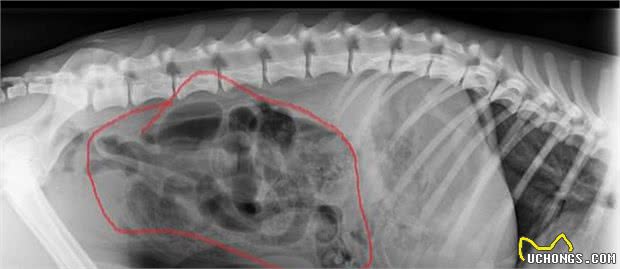

▲德克斯特身体内的异物

来源于特丁顿的格里芬老先生说:“有四次,德克斯特急必须剖腹产查验,也就是在腹腔开一个大创口来查验身体内的任何人体器官。一旦找到异物,就把肠道割开,取下异物,随后再把肠道缝回家。在手术缝合以前,全部别的人体器官都需要接纳查验。这也是一场殊死较量,也需要承担较大的痛楚。有一次,它吃了12块朱古力,这针对它而言但是致命性的啊,幸亏发觉地立即。我常常能看到德克斯特,因为它常常得病。”